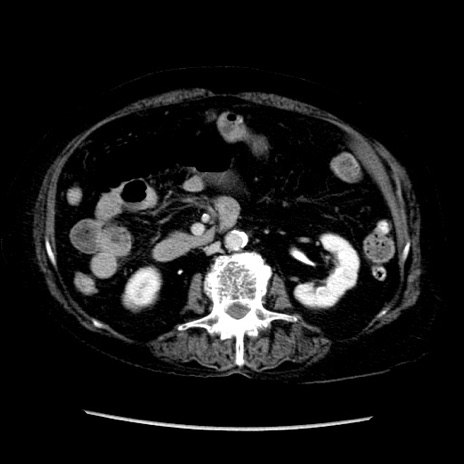

症例14(横断像)

【症例】 90歳代女性

【主訴】 腹痛・嘔吐

【現病歴】今朝から左側腹部痛を認めた。 経過観察していたが、嘔吐を認めたため来院。

【既往歴】 子宮癌術後

【身体所見】 意識清明、BP 127/54mmHg、P 98bpm Sp02 95%(RA)、BT 35.8°C、腹部平坦・軟腸ぜん動音聴取良好、右下腹部圧痛(+) 反跳痛なし

【データ】WBC 9800、CRP 0.46